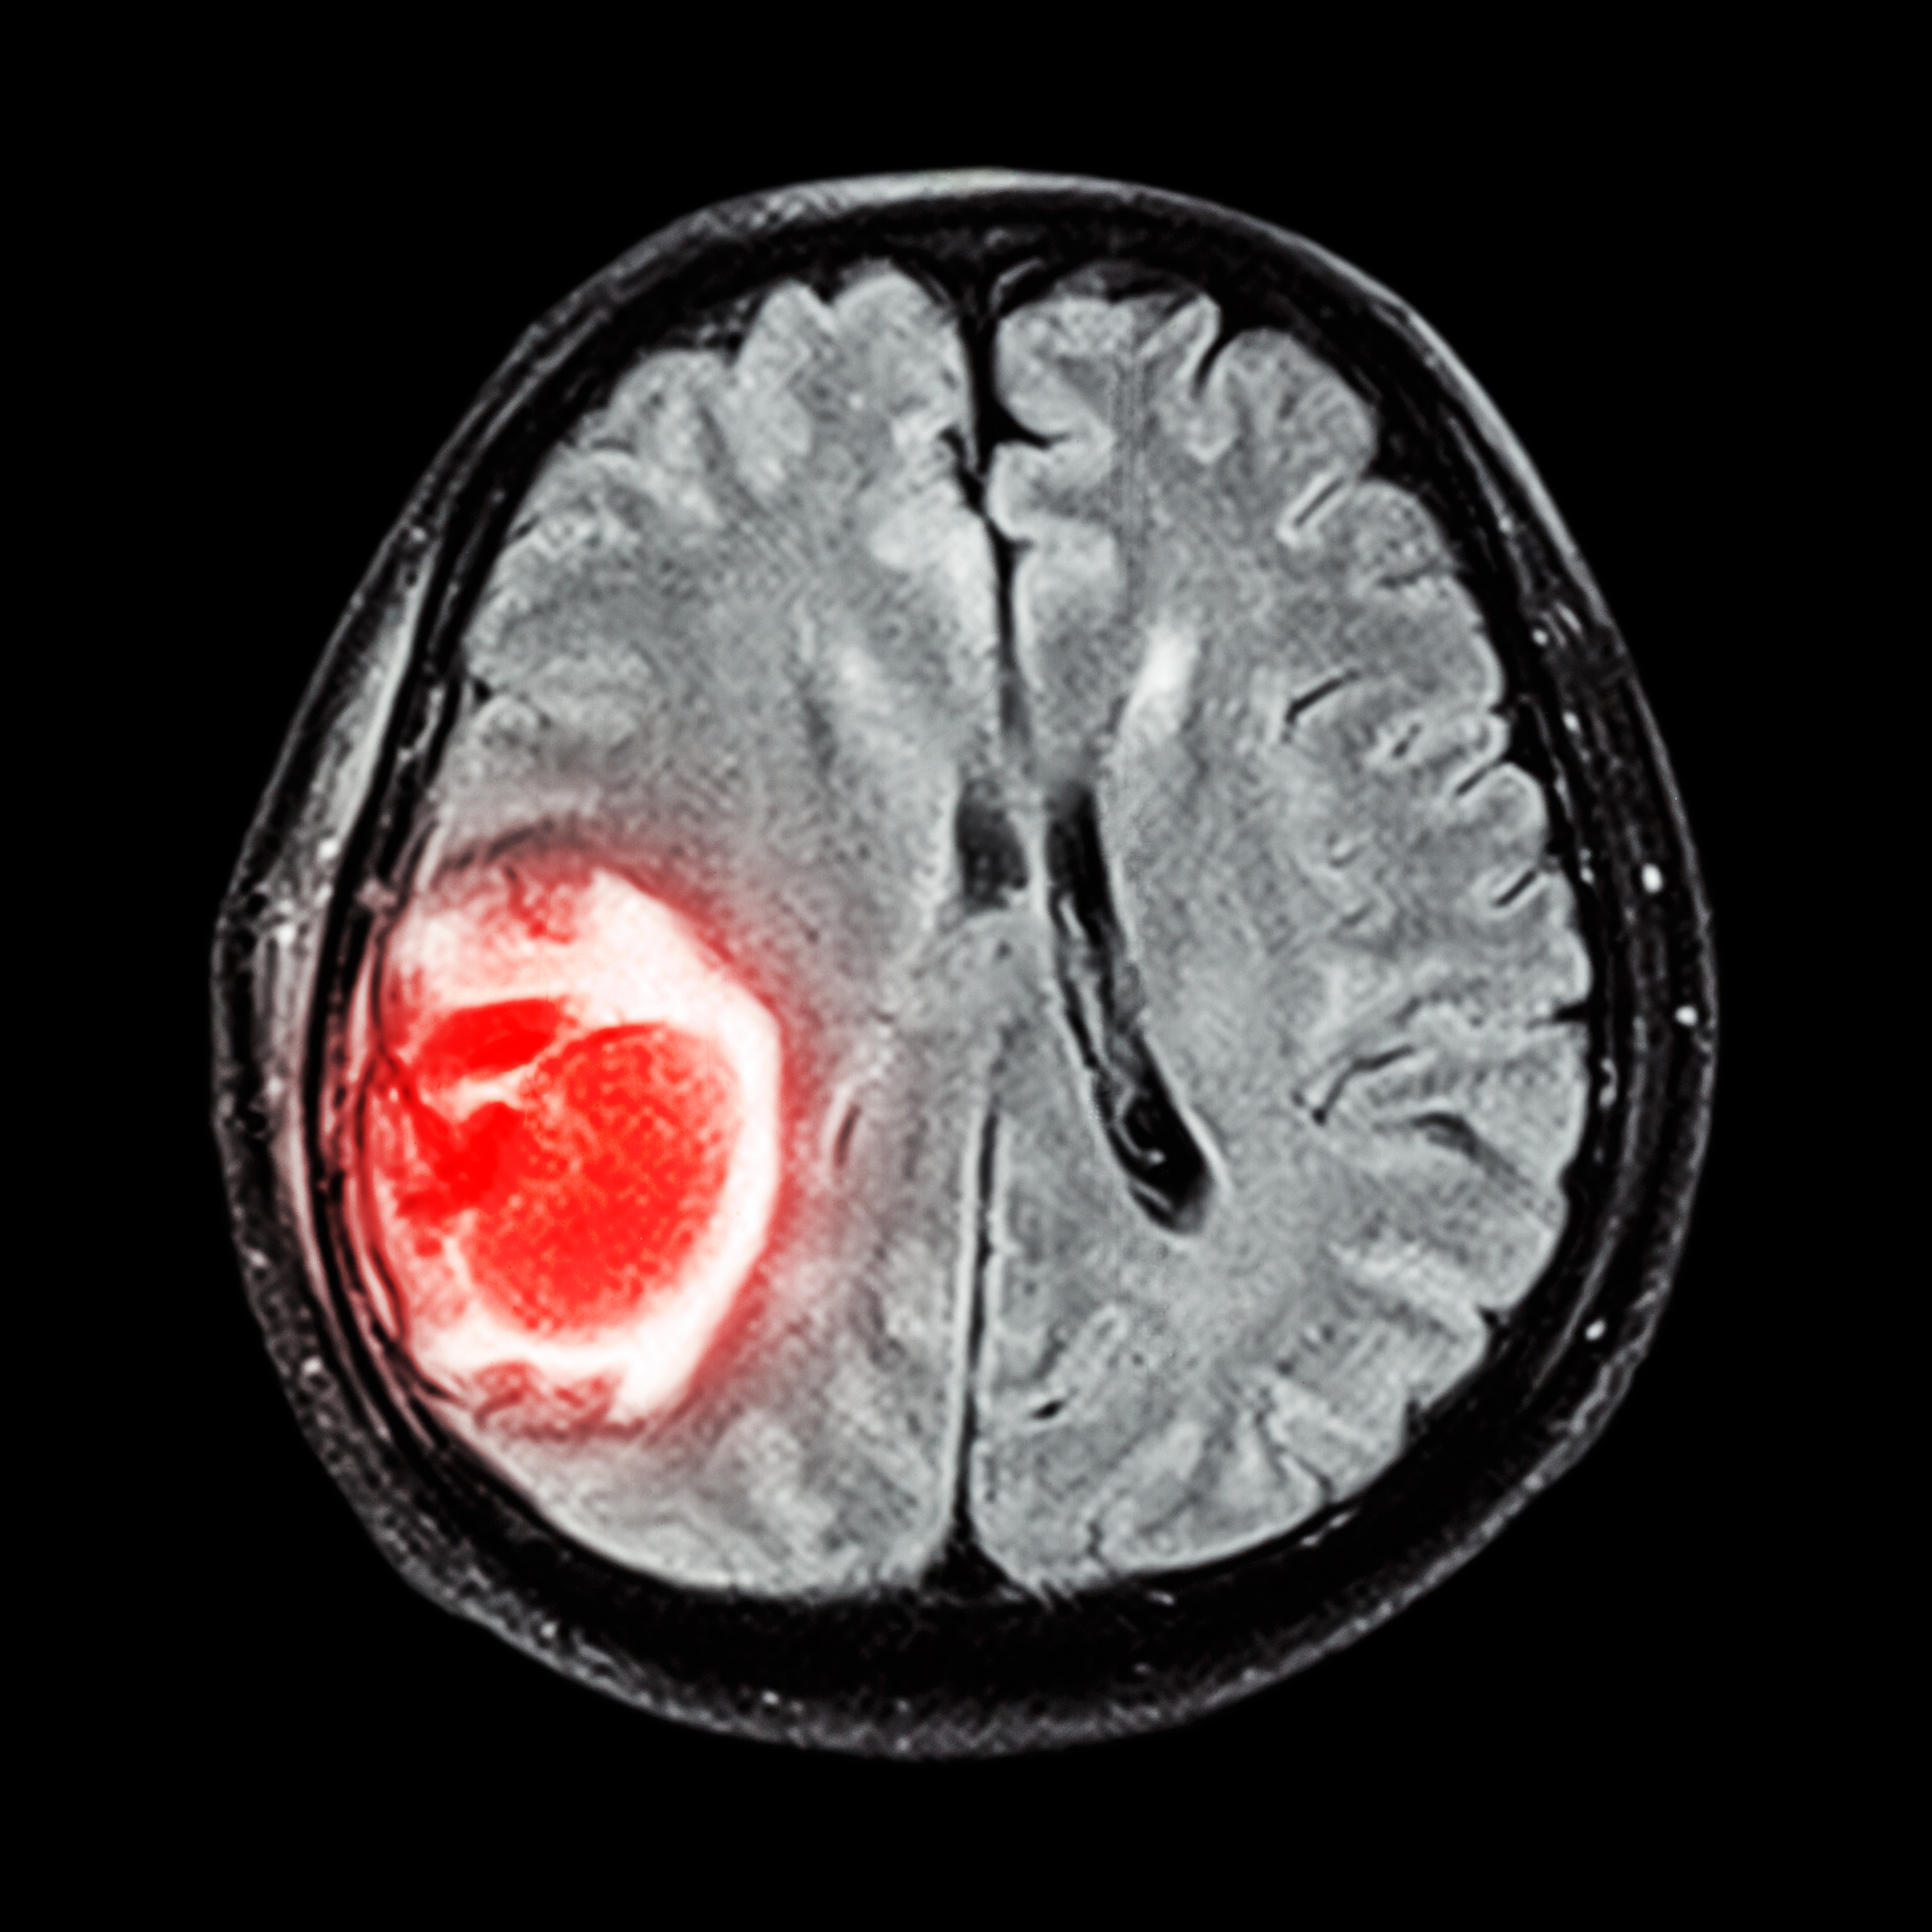

Previous Image Next Image MRI brain : show brain tumor at right parietal lobe of cerebrum MRI brain : show brain tumor at right parietal lobe of cerebrum Share this: Share on X (Opens in new window) X Share on Facebook (Opens in new window) Facebook Like Loading...